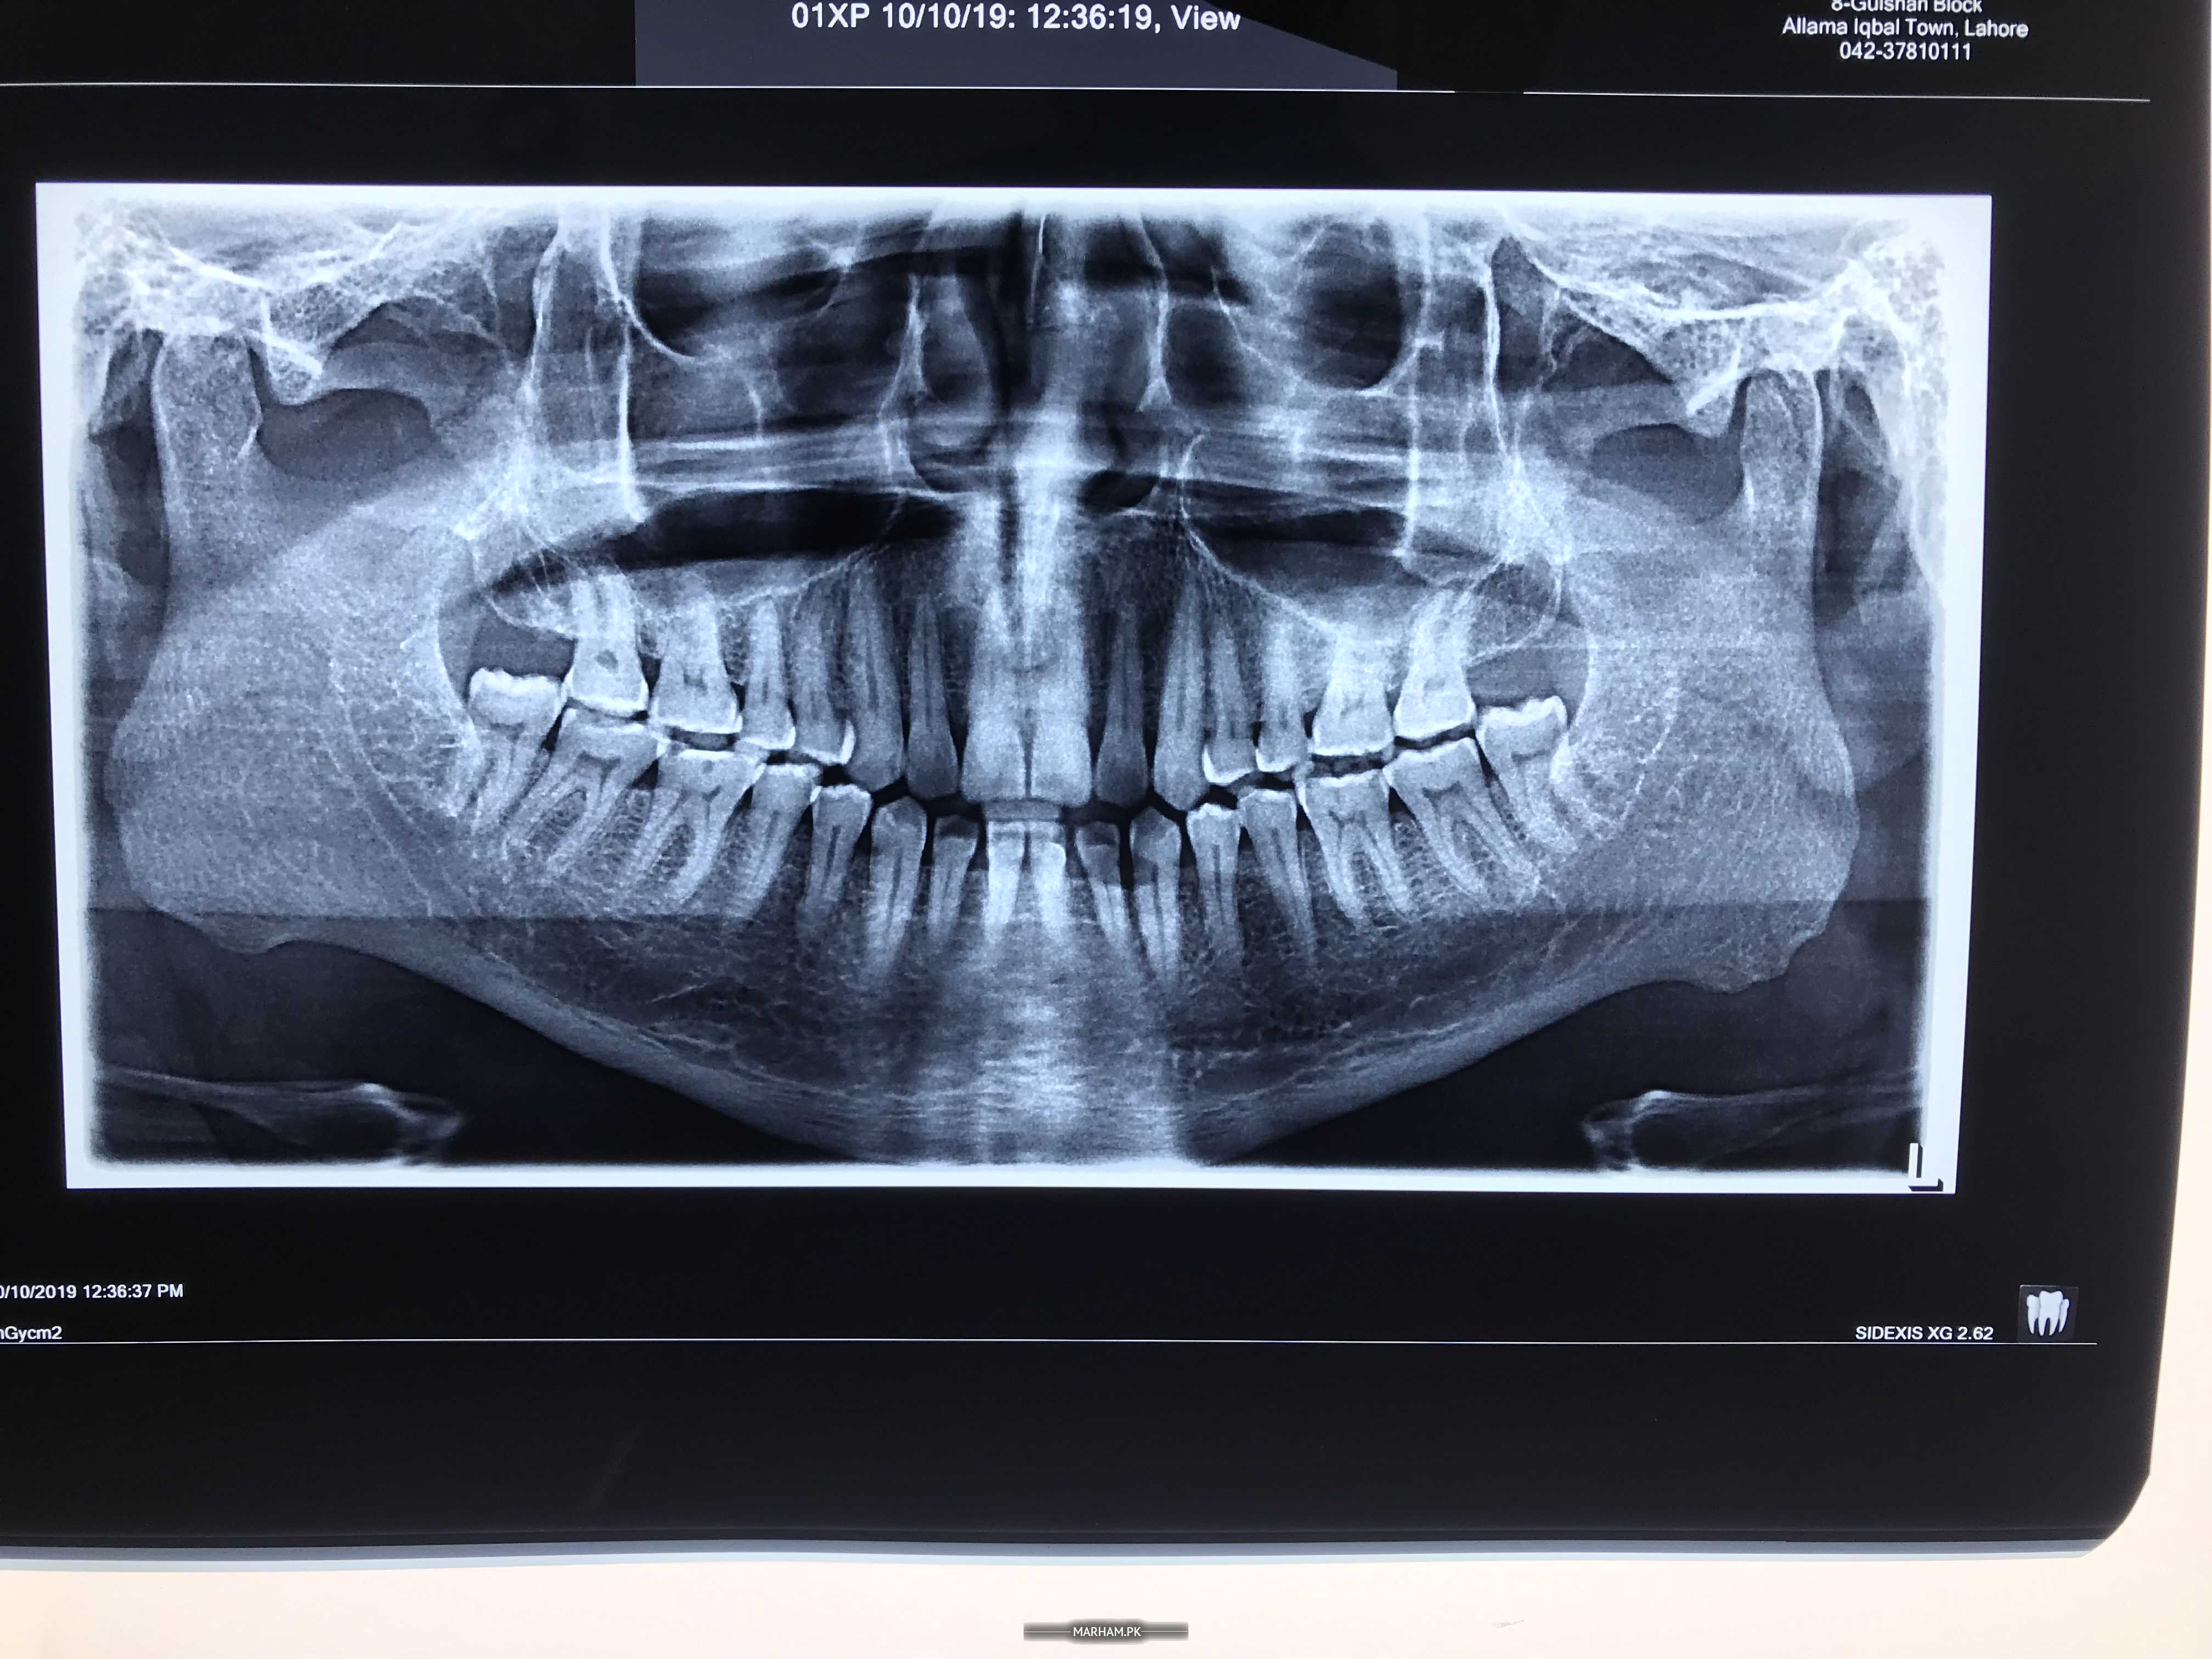

dr if we see that our teeth & gums r ok or not which type of x ray do u recommended

OPG

you will get full info about your each and every tooth

Periapical X-ray for that particular tooth or we can go for OPG which shows all teeth

opg give you detail of all teeth n associate structures

a detailed examination by dentist and opg can help to analyse all the teeth related issues

is opg xray for gums & teeth

how much cost for opg in private or in dental hospital